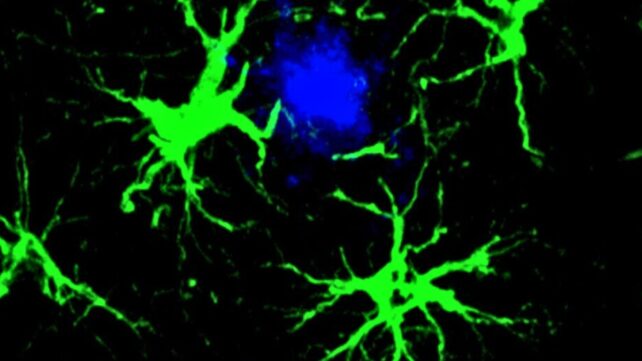

Even in mice with existing amyloid plaques, one injection of the gene therapy was associated with a roughly 50 percent reduction in plaques, the researchers report.

In the new study, researchers focused on star-shaped brain cells called astrocytes, which they engineered to hunt down the amyloid beta proteins associated with cognitive decline in Alzheimer's.

Upon receiving this new assignment, astrocytes became singularly focused on clearing out amyloid beta plaques, a task at which they proved adept.

Even in older mice whose disease was already underway, the treatment was associated with improvement. Older mice who received the gene therapy at six months of age had about half as many plaques by nine months as those in an age-matched control group, which received a virus missing the CAR gene.